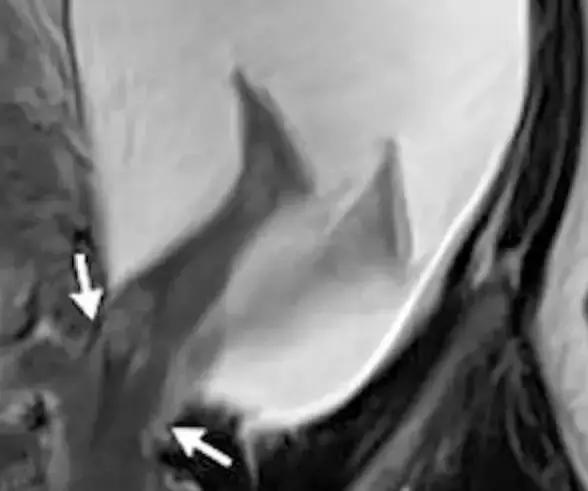

该名妈妈的磁共振扫描(MRI)照片可以看到,箭头所指之处就是宝宝的双脚,而子宫壁处在怀孕初期已有2.5cm大的撕裂,使得部分装着发育中宝宝的羊膜囊露出子宫,宝宝也因为胎动刚好把脚伸出去,造成惊人的景象。

医生表示,通常子宫壁撕裂对导致疼痛与出血,但宝宝的脚伸出去刚好可以帮忙止血,当时发现时,子宫壁已经增加撕裂到5cm,宝宝的双脚跟腹部都已经在子宫外,随即进行剖腹生产,所幸母子均安。